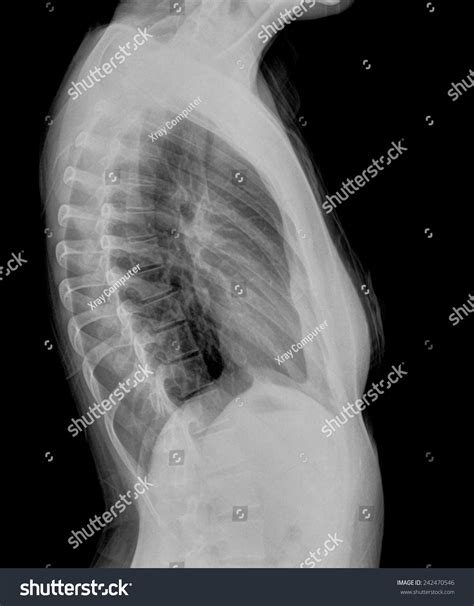

The sternum X ray procedure is quick and painless. Here is a step-by-step overview:

1. The patient is positioned standing or sitting in front of the X-ray machine.

2. The technician will position the X-ray machine to capture images of the sternum from different angles.

3. The patient is asked to hold still and may be instructed to take a deep breath and hold it briefly to minimize movement.

4. The X-ray machine emits a small amount of radiation to produce images of the sternum.

5. The entire process usually takes only a few minutes.

After the images are captured, the patient can resume normal activities immediately.